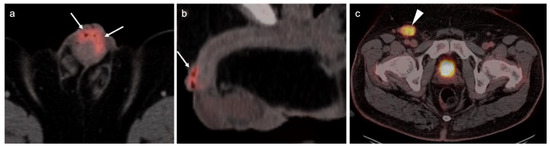

3.1. Prostate Cancer